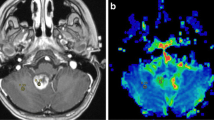

DSC-PWI was analyzed with a dedicated software package (Olea SPHERE®, Olea Medical®, La Ciotat, France). Parametric maps of cerebral blood flow (CBF) and CBV were then obtained using the standard truncated singular value decomposition algorithm (sSVD) for deconvolution [16] and an automatic method to obtain the arterial input function (AIF). The same method was applied to calculate the permeability K2 maps [7]. K2 is the capillary transfer constant describing the movement of contrast from extravascular space back into vessels. In order to avoid the underestimation of CBV due to contrast leakage through the damaged blood brain barrier in tumors, a mathematical correction of leakage was applied to CBV maps. Therefore, the corrected CBV map derived from K2 permeability maps were obtained. Perfusion parametric maps were co-registered to postcontrast axial T1-weighted images. CT perfusion maps of CBF, CBV and PS were computed using a commercially available delay-insensitive deconvolution software (CT Perfusion 4D, GE Healthcare, Milwaukee, Wisconsin). Arterial and venous time-attenuation curves were measured positioning 2 × 2 voxels (in-slice) Regions of Interest (ROIs), respectively, on the basilar artery, internal carotid artery, on anterior cerebral artery and on the posterior superior sagittal sinus. CTP CBF, CBV and PS maps were calculated by deconvolving the arterial time-attenuation curve with the tissue time-attenuation curve with a two-compartmental model. Average CTP maps were created by averaging the cine (dynamic) CTP source images over the duration of the first pass of contrast. Large blood vessels were automatically excluded from calculation by the software [17, 18]. As shown in Fig. 1, two different regions of interest (ROI) larger than 1 cm2 were manually drawn on contrast-enhanced T1-weighted images and on average CTP images that were co-registered with DSC-PWI and CTP parametric maps, respectively. Average CTP images were chosen due to their optimal contrast resolution of tumor borders. The first ROI was drawn on every section in which the enhancing or non-enhancing tumor solid tissue was visible, avoiding necrotic and cystic areas, and carefully selecting the matching CT and MR slices. The second ROI, mirroring the tumor region, was delineated on the apparently normal brain tissue on the contralateral hemisphere. Regional CBF, CBV and K2 and PS absolute levels were measured in both tumor and apparently normal tissue. Normalized values both for DSC-PWI (PWI nCBF; PWI nCBV; and PWI nK2) and CTP (CTP nCBF; CTP nCBV; and CTP nPS) were then obtained by dividing tumor and contralateral absolute levels. CBF, CBV, K2 and PS values were expressed in mL/100 g/min, mL/100 g, s and mL/100 g/min, respectively.

Tumor lesion segmentation on magnetic resonance dynamic susceptibility contrast perfusion-weighted imaging (PWI) and computed tomography perfusion (CTP) in a 43-year-old patient with low-grade glioma (Diffuse Astrocytoma IDH-mutant) located in left insular lobe (Panel A) and in a 61-year-old patient with high-grade glioma (Glioblastoma IDH-wildtype) placed in left temporal lobe (Panel B)